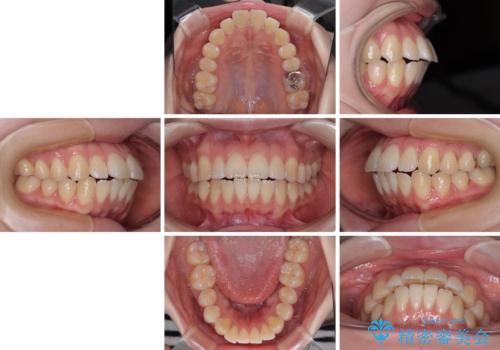

飛び出した前歯を引っ込める ワイヤー装置での抜歯矯正治療

- くちばしのように飛び出した前歯を気にして来院された患者様です。

上下左右の第一小臼歯4本を抜歯して、ワイヤー装置にて矯正治療を行うこととしました。

舌の突出癖により、口元が突出しているだけでなく、上下前歯が非接触となっておりました。

舌のトレーニングをしっかりと行っていただくことで、2年を切って治療を終えるとともに

、上下前歯を接触させることができました。